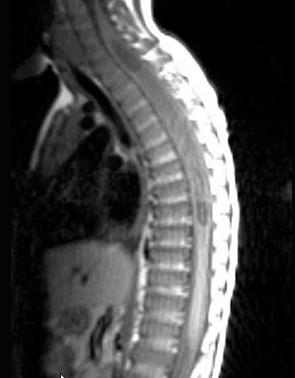

常见的椎管内肿瘤(如图所示)有()A.脊膜瘤B.胶质瘤C.血管瘤D.上皮样囊肿E.神经鞘瘤

问题 常见的椎管内肿瘤(如图所示)有()

选项 A.脊膜瘤 B.胶质瘤 C.血管瘤 D.上皮样囊肿 E.神经鞘瘤

答案 ABCDE